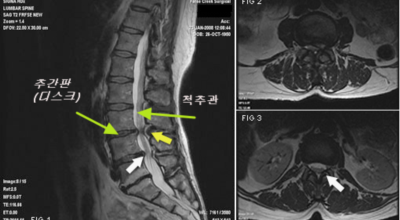

요추관 협착증은 척추 내 신경이 지나가는 통로가 좁아지는 현상으로 기인해서 신경이 눌리면서 이에 따른 여러가지 증상을 유발하는 질환을 의미해요.

허리 협착증은 이렇게 주로 허리통증과 또한 다리 통증이 동반되는 질환인데, 허리 협착증 증상은 허리디스크와 비슷하지만 사실 완전히 다른 질환이라고 할 수 있어요. 기온이 낮은 겨울철이나 야외활동이 적은 요즘같은 시기에는 인체 움직임이 떨어지게되면서 허리 주변의 근육과 인대가 긴장하게 되고 약화되어 허리 질환의 발생률도 높아지게 되어요. 이렇듯 허리통증 뿐만 아니라다리저림 증상까지 함께 나타난다면 허리 협착증을 의심해 볼 수 있어요.

허리 협착증은 척추관이 좁아지게 되면서 신경을 압박하게 되어 허리통증과 또한 다리에도 여러가지 증상을 일으키게 되는데, 발생 원인은 주로 노화로 인한 퇴행성 변화가 많았지만 요즈음는 옳지 않은 자세로 오랫동안 앉아있는 사람들이 많아지면서 생기는 경우도 많아졌으며, 선천적인 요인으로 나타나는 경우도 있답니다.